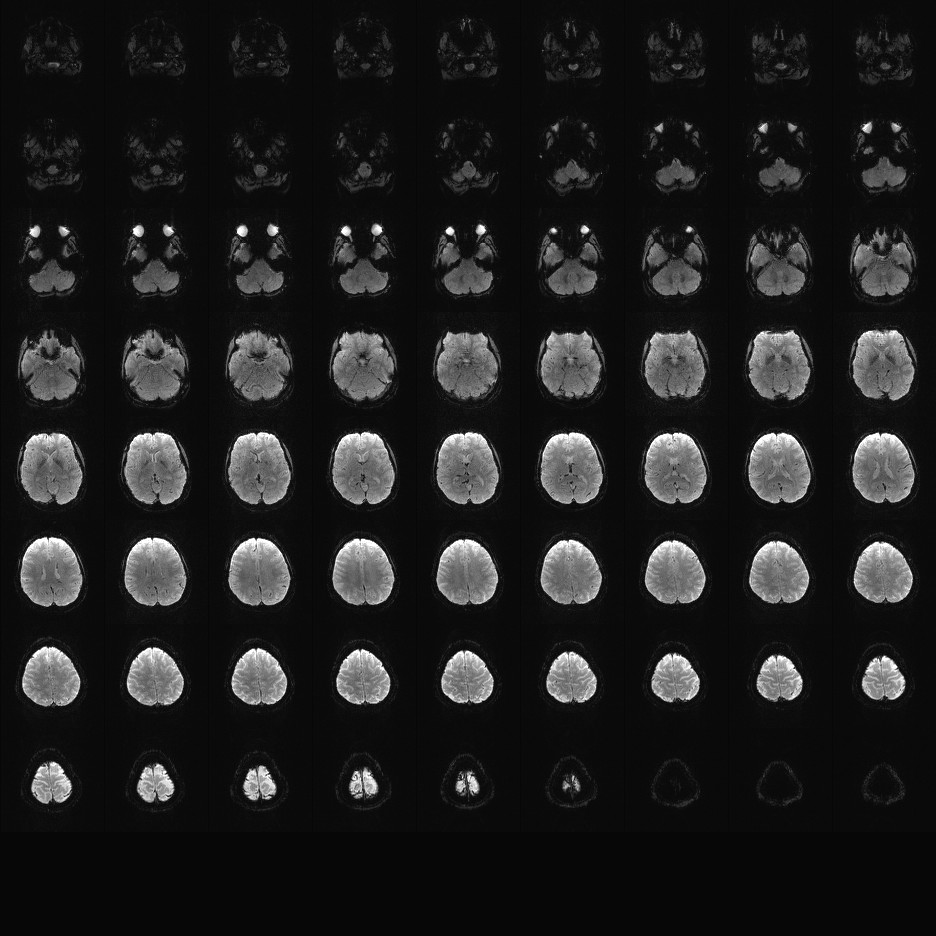

Multi-banded RF pulses can be used to accelerate volume coverage along the slice direction by simultaneously exciting and acquiring multiple slices and subsequently unaliasing them using parallel imaging principles and the spatial information available in multi-channel RF array coils.

This allows for a direct reduction in the volume TR by the number of simultaneously excited slices (i.e., the multiband (MB) factor or the slice acceleration factor).